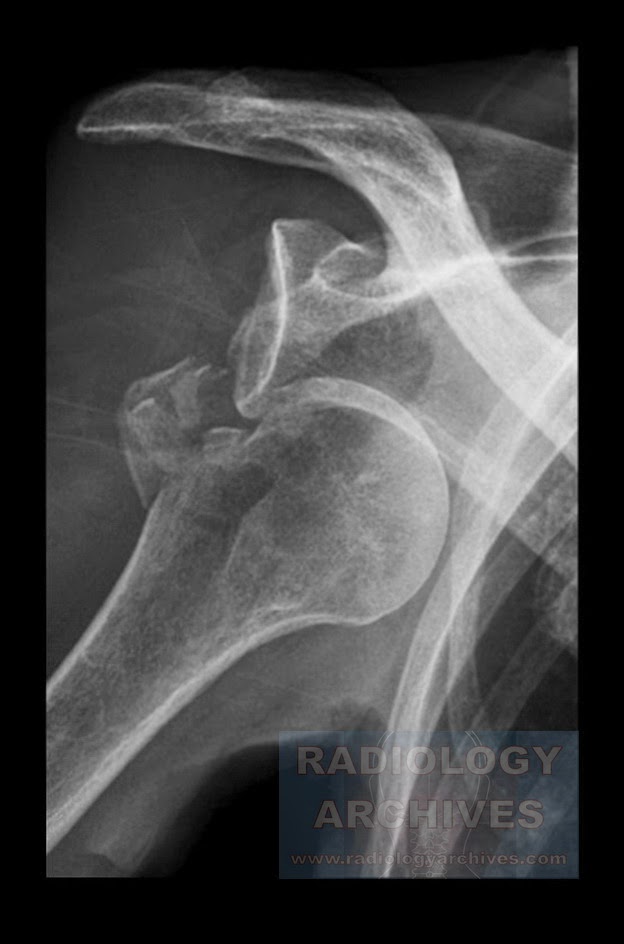

From www.radiologyarchives.com

Radiology Archives Βλάβη Hill Sachs* (Πρόσθιο Εξάρθρημα Ώμου με What Is A Hill Sachs Fracture The humeral head ‘collides’ with the anterior part of the glenoid, causing a lesion,. This injury causes bone damage to the ball of the shoulder joint. Is a compression fracture of the posterolateral humeral head due to its compression against. What Is A Hill Sachs Fracture.

Hill Sachs Lesion